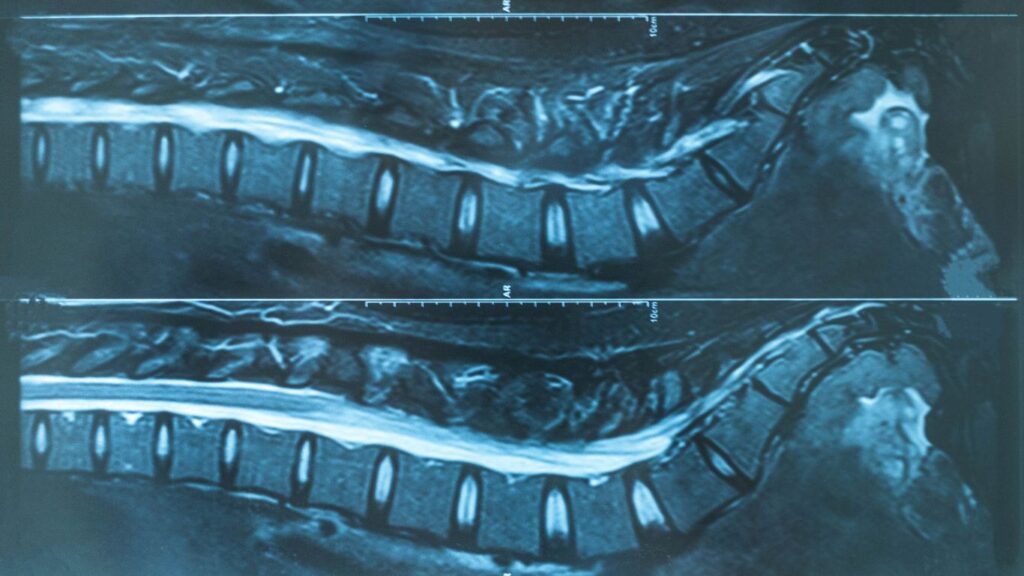

Tomografía Lumbosacra: Diagnóstico Preciso en Querétaro

La tomografía lumbosacra es una técnica avanzada de diagnóstico por imágenes que permite evaluar con precisión la parte baja de la columna vertebral y los tejidos circundantes. Este examen es esencial para detectar condiciones que afectan la salud de la columna, proporcionando información vital para el tratamiento adecuado. En Altaria, contamos con equipos de última […]